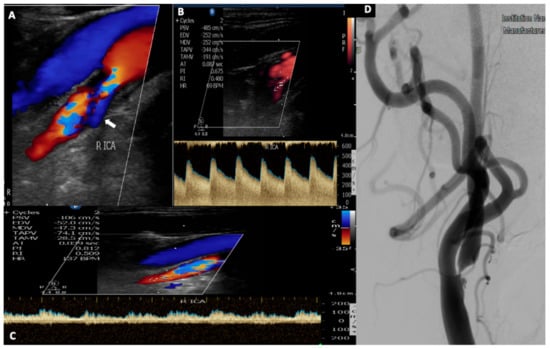

3. Vertebral Artery